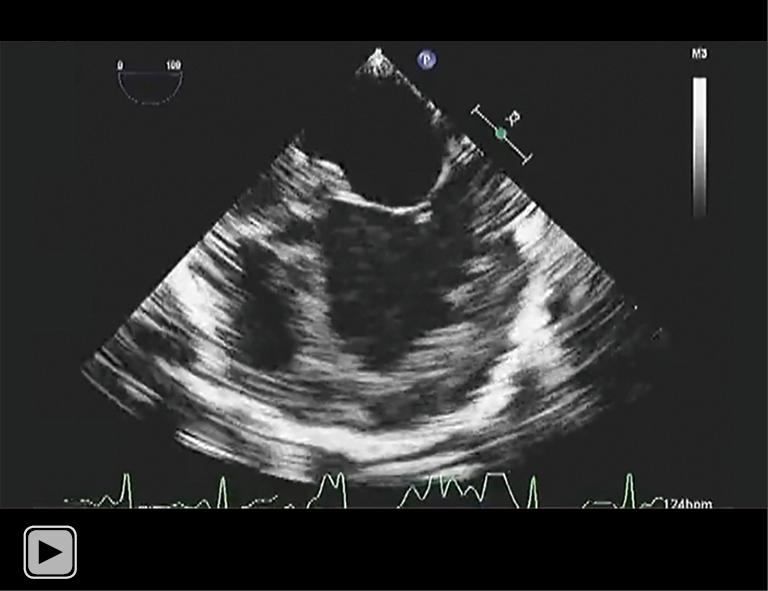

Pulmonary artery banding (PAB) may reduce the need for left ventricular assist devices and heart transplantation in children with end-stage heart failure. However, excessive banding may increase the right ventricular afterload, leading to worsening of heart failure. The estimated right ventricular pressure and the shifting of the interventricular septum by transesophageal echocardiography (TEE), pulmonary artery pressure, right atrial and ventricular pressure, percutaneous oxygen saturation, and mixed venous oxygen saturation are utilized to determine the optimal circumference for PAB. Here, we report the case of a 5-month-old patient with end-stage heart failure due to left ventricular noncompaction cardiomyopathy (LVNC), with a gene mutation of MYH7, who underwent successful PAB. The exact PAB placement was additionally guided by using cerebral regional oxygen saturation (rSO) measurement to achieve a tolerable and optimal PAB effect. We monitored rSO and other hemodynamic parameters while surgeons banded the pulmonary artery to achieve both highest rSO levels and stable hemodynamics. rSO was 68% before banding, and increased and remained at over 90% after the banding at same FiO. Patient's heart failure improved gradually, and the child was discharged home at 6 months after PAB. The rSO is a simple and non-invasive monitor for the measurement of oxygen delivery to the brain tissue. rSO alone would not be able to guide PAB placement in the vulnerable DCM patients, but it may be of one further monitoring value for the optimal pulmonary artery circumference while patients are undergoing PAB.

肺动脉环缩术(PAB)可能会减少终末期心力衰竭儿童对左心室辅助装置和心脏移植的需求。然而,过度环缩可能会增加右心室后负荷,导致心力衰竭恶化。通过经食管超声心动图(TEE)评估右心室压力和室间隔移位、肺动脉压力、右心房和心室压力、经皮血氧饱和度以及混合静脉血氧饱和度,以确定PAB的最佳环缩周长。在此,我们报告一例5个月大的因左心室致密化不全心肌病(LVNC)导致终末期心力衰竭的患者,其存在MYH7基因突变,该患者成功接受了PAB。通过使用脑局部血氧饱和度(rSO)测量来额外指导PAB的精确放置,以实现可耐受且最佳的PAB效果。在外科医生对肺动脉进行环缩时,我们监测rSO和其他血流动力学参数,以实现最高的rSO水平和稳定的血流动力学。环缩前rSO为68%,在相同FiO情况下,环缩后rSO升高并维持在90%以上。患者的心力衰竭逐渐改善,PAB术后6个月患儿出院。rSO是一种用于测量脑组织氧输送的简单且无创的监测方法。单独的rSO无法指导脆弱的扩张型心肌病患者进行PAB放置,但在患者接受PAB时,它可能对确定最佳肺动脉环缩周长具有进一步的监测价值。